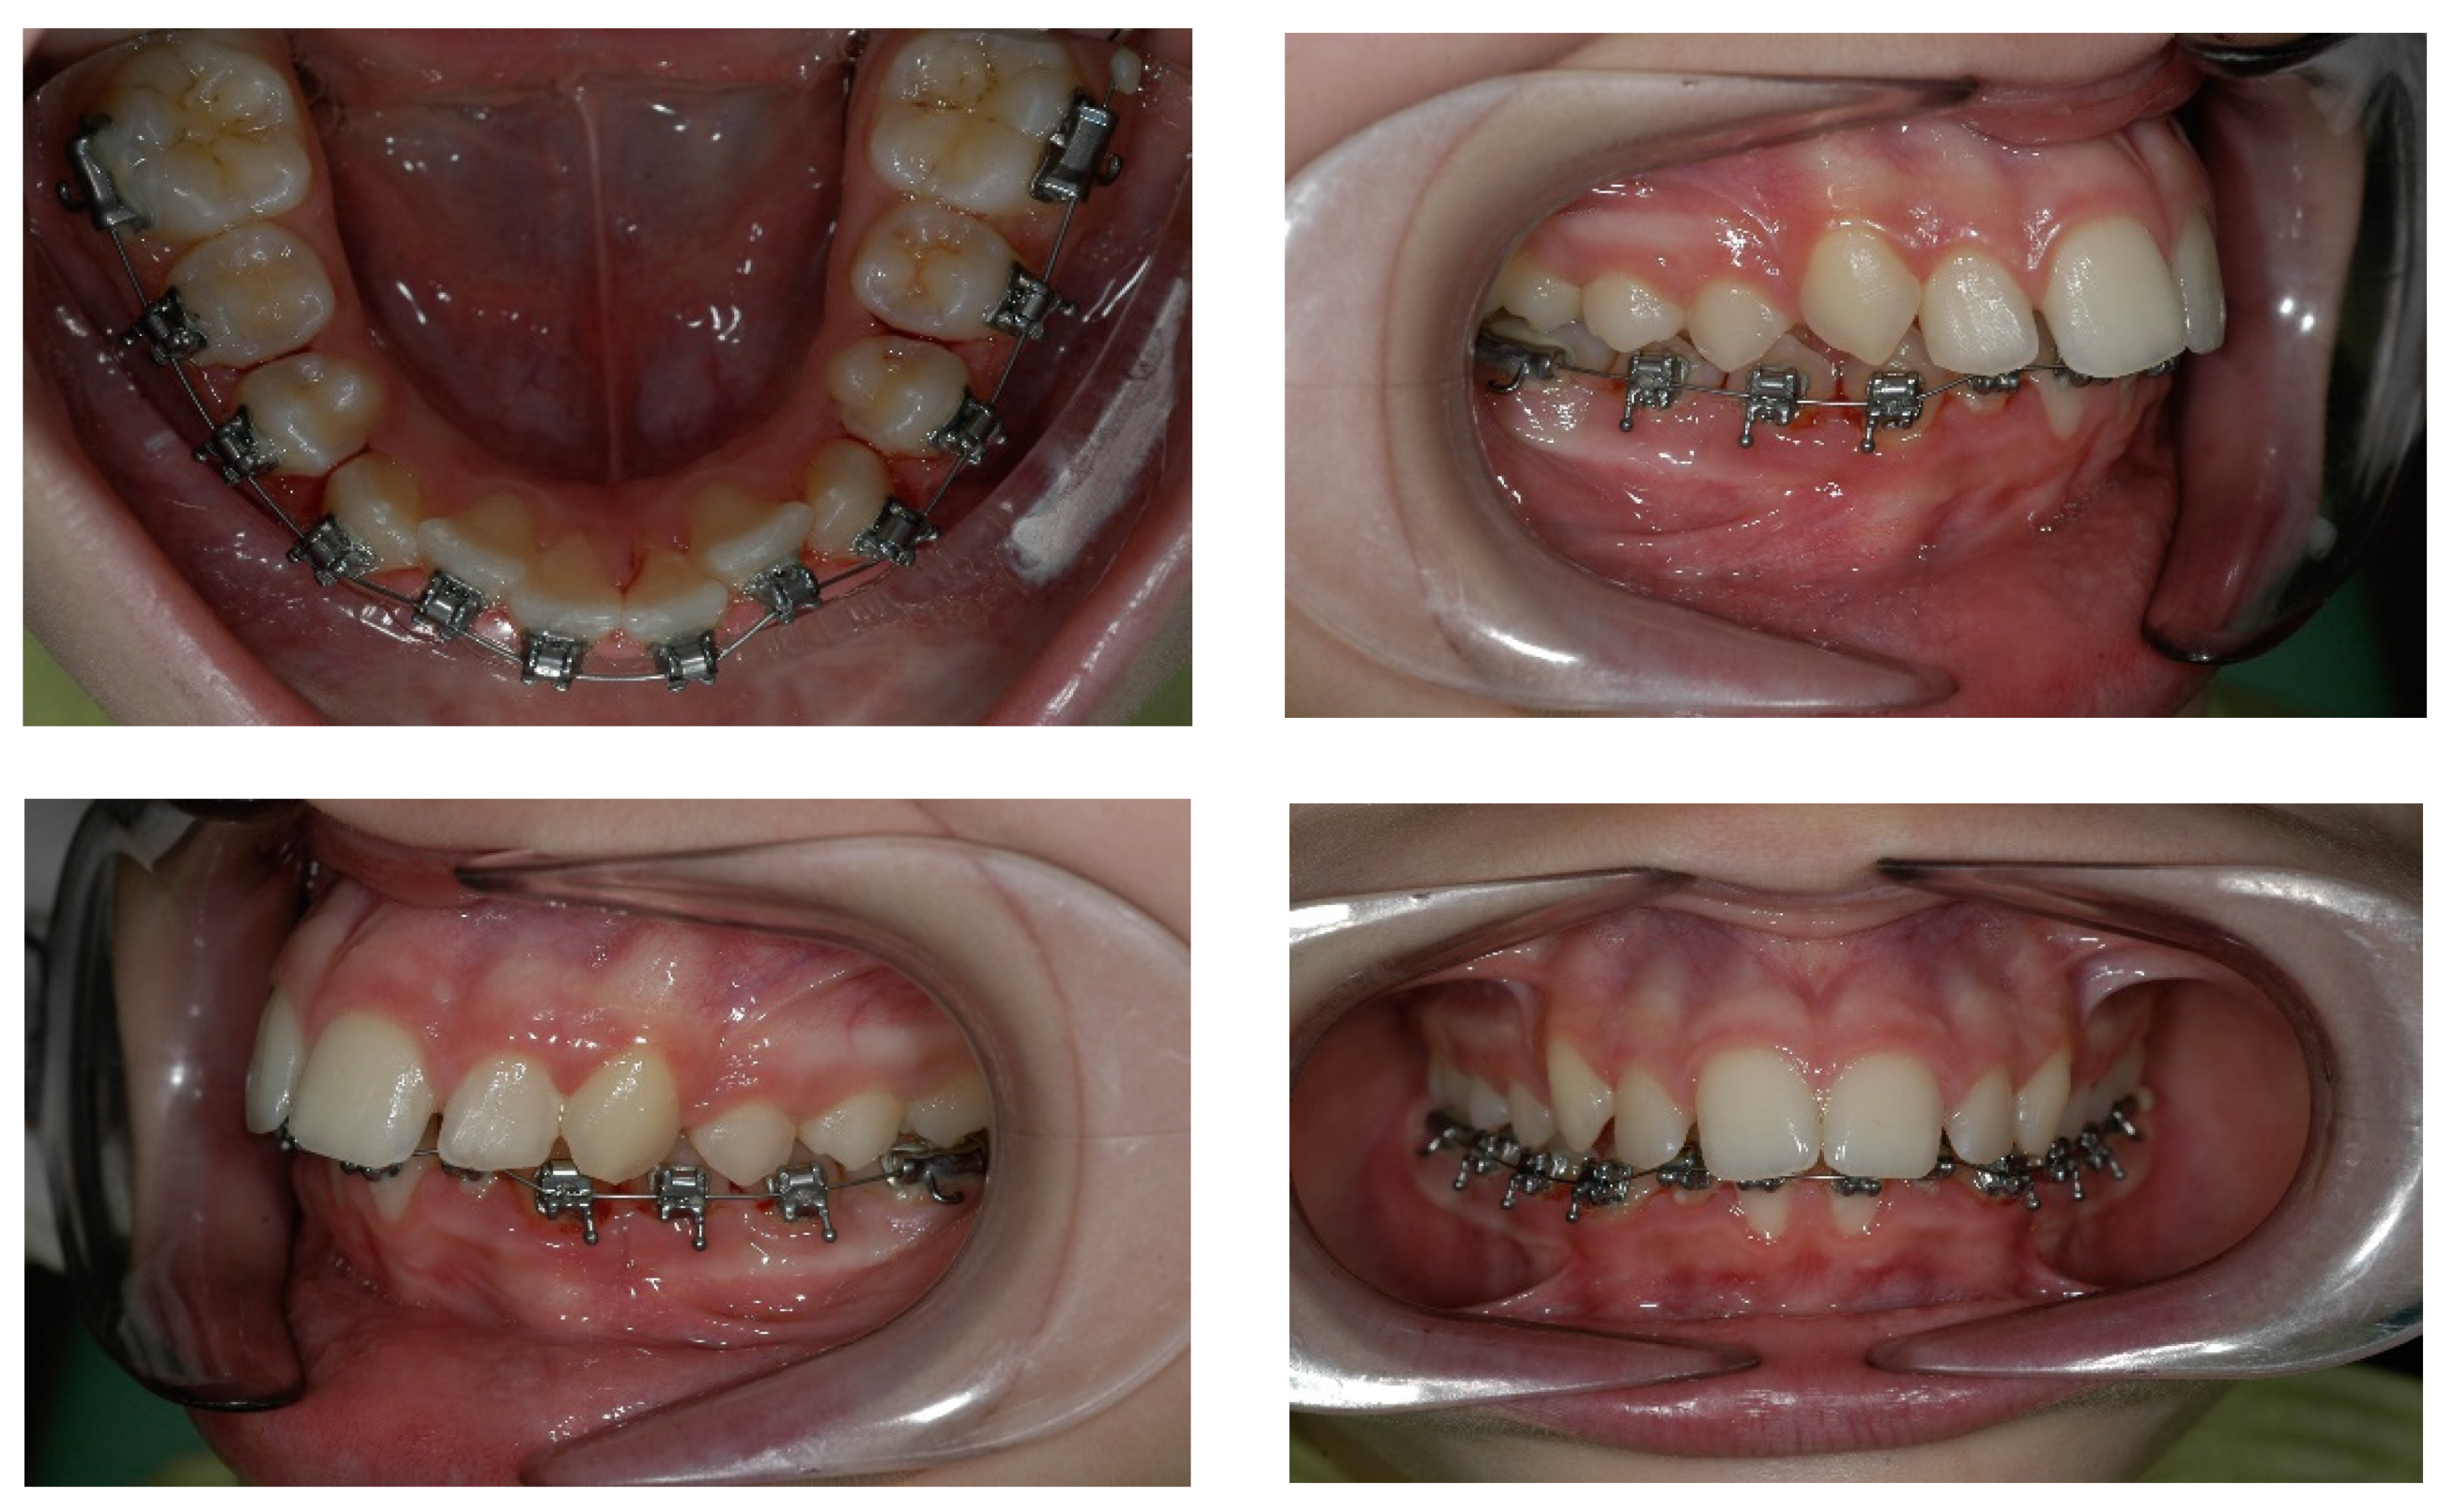

4. Case Report

4.3. Treatment Strategy

4.4. Treatment Progress